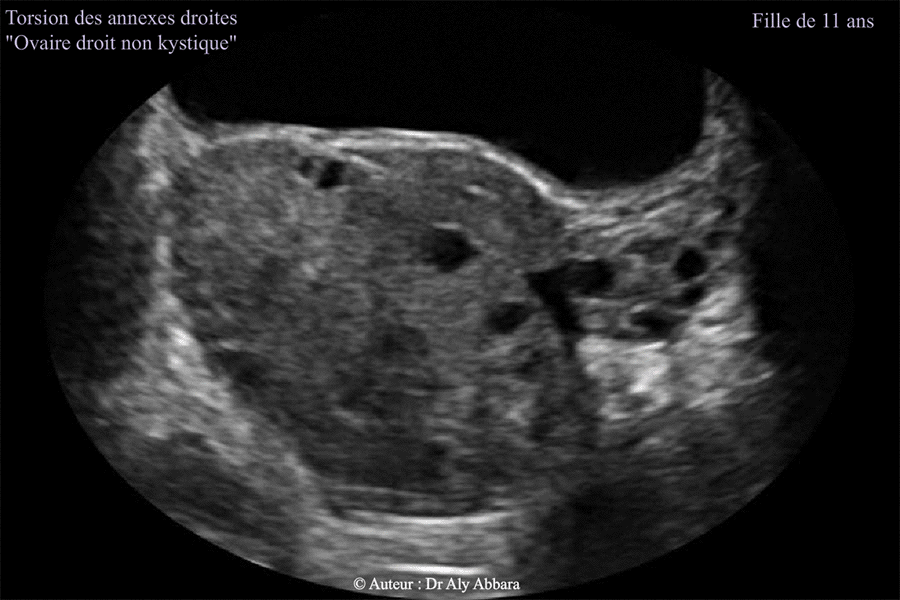

J0 :

Images échographiques montrant une torsion des annexes utérines droites chez une fille de 11 ans (non encore réglée : pas de ménarche) - ovaire droit non kystique.

L'image présentée compare l'aspect l'ovaire droit tordu et l'ovaire gauche non tordu.

L'image échographique montre un ovaire droit augmenté de volume (73 cm3 contre 8 cm3 qui est le volume de l'ovaire gauche non tordu). On observe la présence des follicules antraux (de 2 à 5 mm de diamètre) dispersés au sein de cet ovaire et séparés par un stroma ovarien œdémateux et infiltré (cliniquement par le sang) et fort probablement nécrobiosé par une ischémie (silence Doppler couleur) due l'obturation mécanique des vaisseaux vascularisant normalement les annexes utérines (torsion de 720° à l'inverse des aiguilles de montre : du ligament utéro-ovarien ; du ligament large et du ligament lombo-ovarien droits).